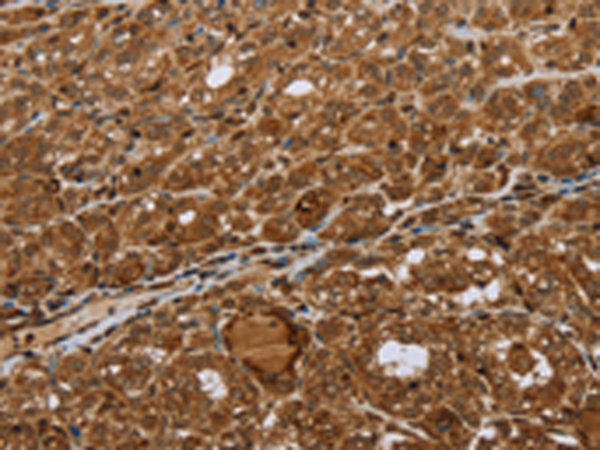

分类: 科研抗体货号: P10998别名: CDF, DIA, HILDA, MLPLI应用: IHC反应种属: Human, Mouse, Rat